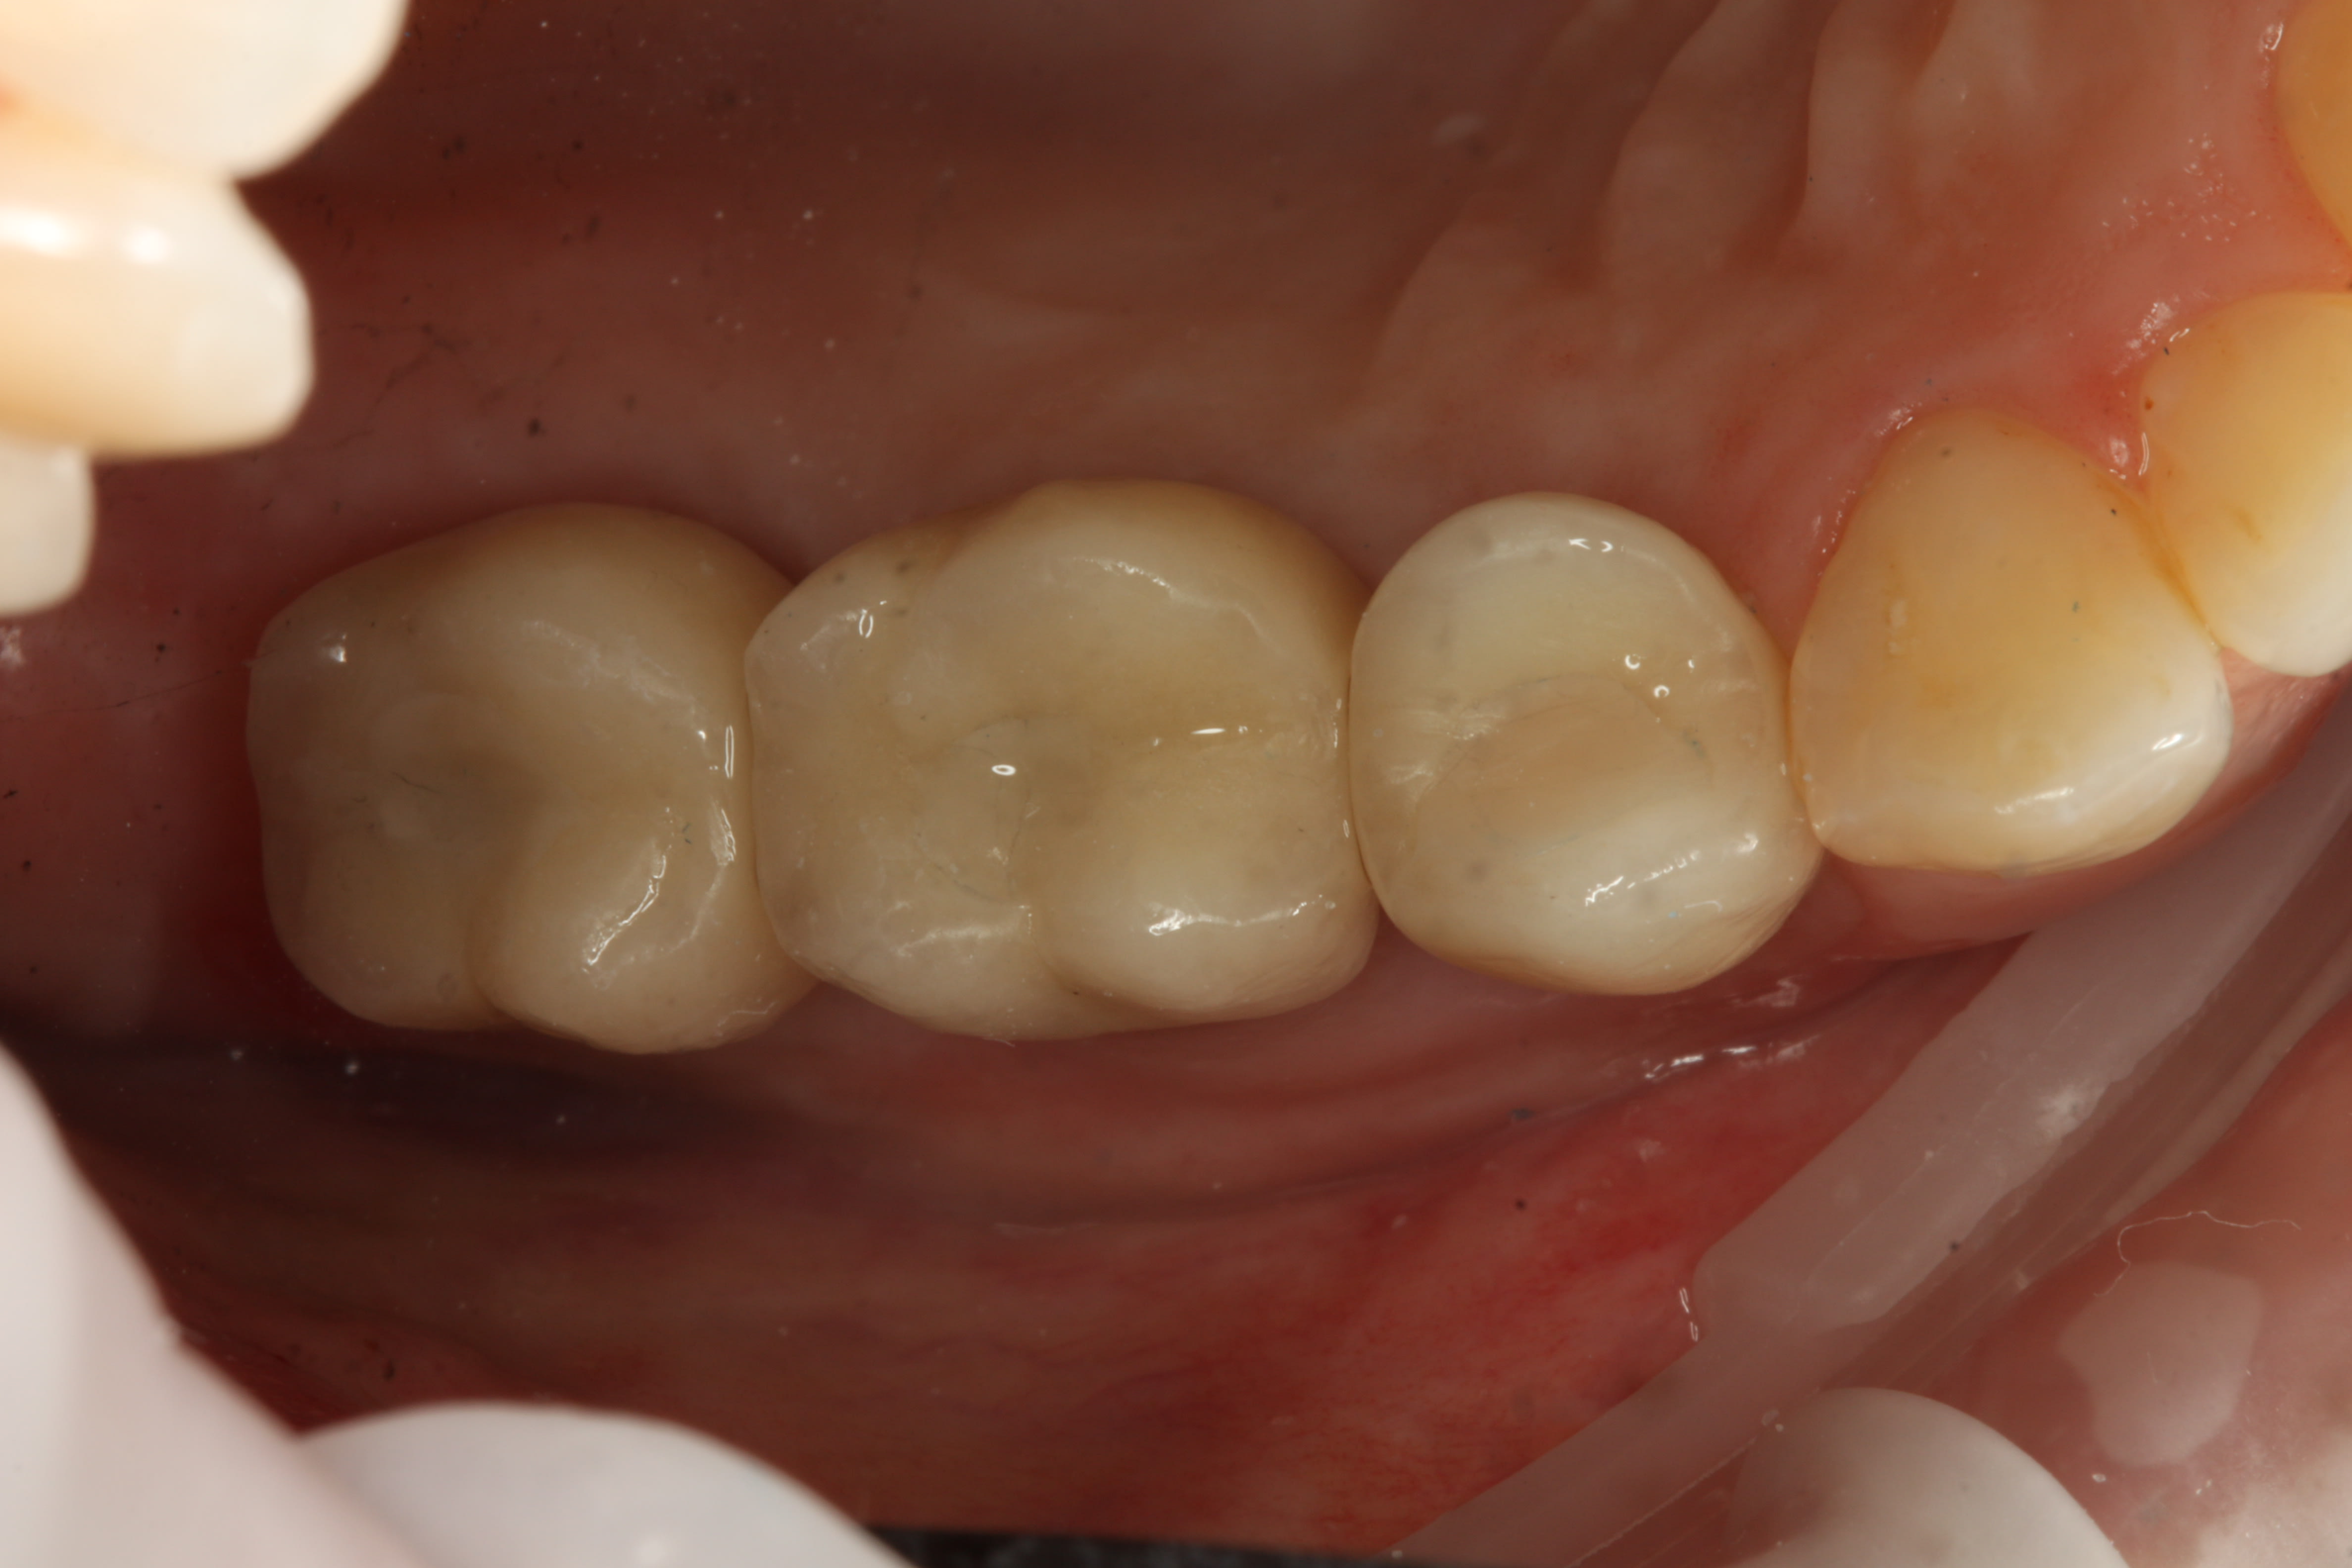

Exo racine région 15

Greffe/expansion zone 14 (que 3 mm d'os au départ)

Pose implants 14-15-16 (il n'y a pas de 7 en bas)

Pose couronnes zircone/céram transvissées

Nobel ASC : Angle Screw Chanel pour la 14, car axe pas top

Fermeture puits téflon-compo